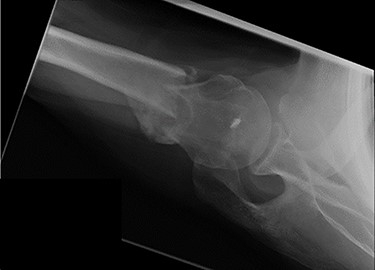

Examination and imaging of the patient revealed that during the fall, he had sustained a left surgical neck of humerus fracture (Fig. 1). Significant skin puckering was noted on the anterior aspect of the left shoulder over the fracture site, otherwise the arm was neurovascularly intact (Fig. 2). He was immediately reviewed by the orthopaedic team who offered surgical fixation of the fracture on the following morning, which was dependent on an appropriate anaesthetic assessment. The patient was in agreement and consented to proceed.

Antero-posterior view X-ray taken on day of admission, showing a left surgical neck of humerus fracture with anterior displacement of the proximal humeral shaft.